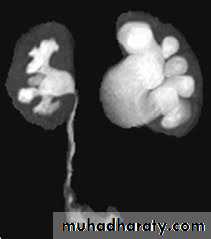

Pelviureteric junction (PUJ)obstruction

A ureteropelvic junction (UPJ) obstruction can be thought of as a restriction to flow of urine, from the renal pelvis to the ureter, which, if left uncorrected, will lead to progressive renal deteriorationUPJ obstruction occurs in all pediatric age groups, but there tends to be a clustering in the neonatal period because of the detection of antenatal hydronephrosis and again later in life because of symptomatic occurrence. At one point about 25% of cases were discovered within the first year of life.

UPJ obstruction is the most common cause of significant dilation of the collecting system in the fetal kidney.

Obstruction occurs more commonly in boys than in girls.Left-sided lesions predominate, particularly in the neonate (approximately 67%).

Bilateral UPJ obstruction is present in 10% to 40% of cases.